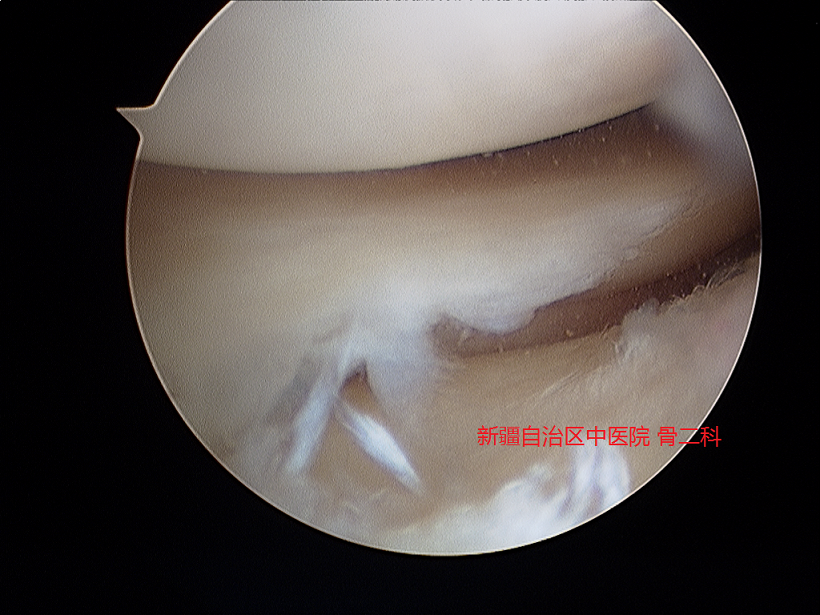

2.损伤的半月板

半月板损伤一般多见于急性外伤和慢性磨损,前侧常见于年轻人,后者多见于老年人。半月板损伤后,膝关节内外侧间隙会出现疼痛,上下楼梯及蹲起不利,严重损伤的患者可发生膝关节交锁,在做某个动作时,膝关节突然卡住不能活动。其根本原因在于破裂的半月板不能继续行使相关功能,照成功能障碍。

更重的半月板损伤,有绞锁症状